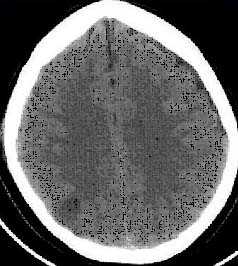

- выявить наличие внутричерепной гематомы (её характер, локализацию, размеры),

- выявить наличие очага ушиба головного мозга (его локализацию, размеры, характер, наличие геморрагического компонента),

- выявить субарахноидальное кровоизлияние,